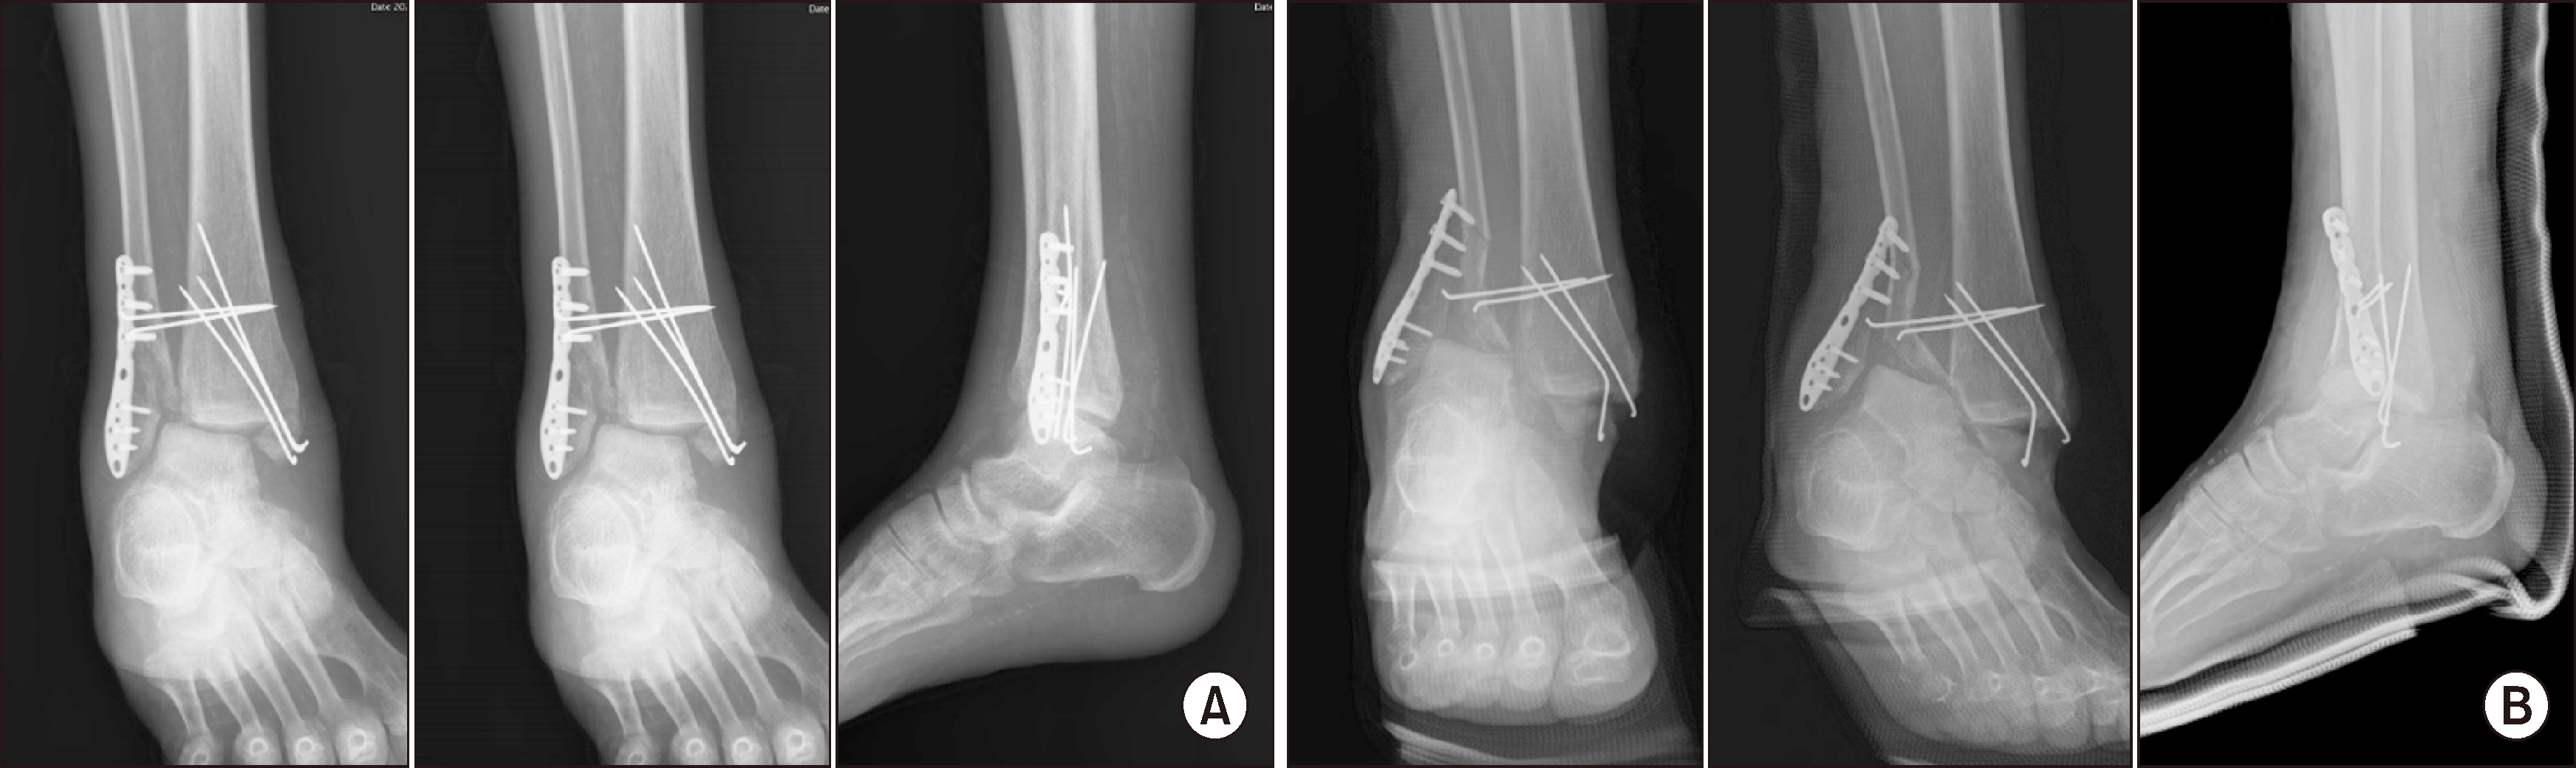

During outpatient follow-up, 8 months post-surgery, the patient exhibited signs of fever and operation site infection, along with evidence of metal loosening, necessitating hospital admission (Fig. 12). Despite the arduous clinical journey, the patient declined the option for a below-knee amputation. Given the ongoing complications, a decision was made to perform comprehensive surgical intervention. In light of evidence of implant-associated infection, metal removal was performed and anti-cement arthroplasty was carried out (Fig. 13). Three months after, this involved the insertion of a vancomycin-mixed cement filling, TTC fusion using a proximal humeral internal locking system (PHILOS) plate (DePuy Synthes) on the lateral side, and additional fixation using a 6.5 TCS (threaded cannulated screw) (Fig. 14).

Follow-up visits were promising: 2 months after TTC fusion, the patient could walk short distances without difficulty (Fig. 15). The most recent follow-up, 2 years post-TTC fusion, showed no major complications. The patient was able to engage in light daily activities. Radiograph images confirmed well-maintained fusion, with the exception of a broken screw in the second from the distal portion (Fig. 16).

Figure 13

Post-operation radiograph following metal removal and anti-cement arthroplasty due to findings of implant-associated infection.

Figure 14

(A) Post-operation radiograph showing vancomycin-mixed cement filling, TTC fusion using a proximal humeral internal locking system (PHILOS) plate on the lateral side, and additional fixation with a 6.5 threaded cannulated screw. (B) Day 10 post-revision TTC fusion medial and lateral clinical pictures. TTC: tibiotalocalcaneal.